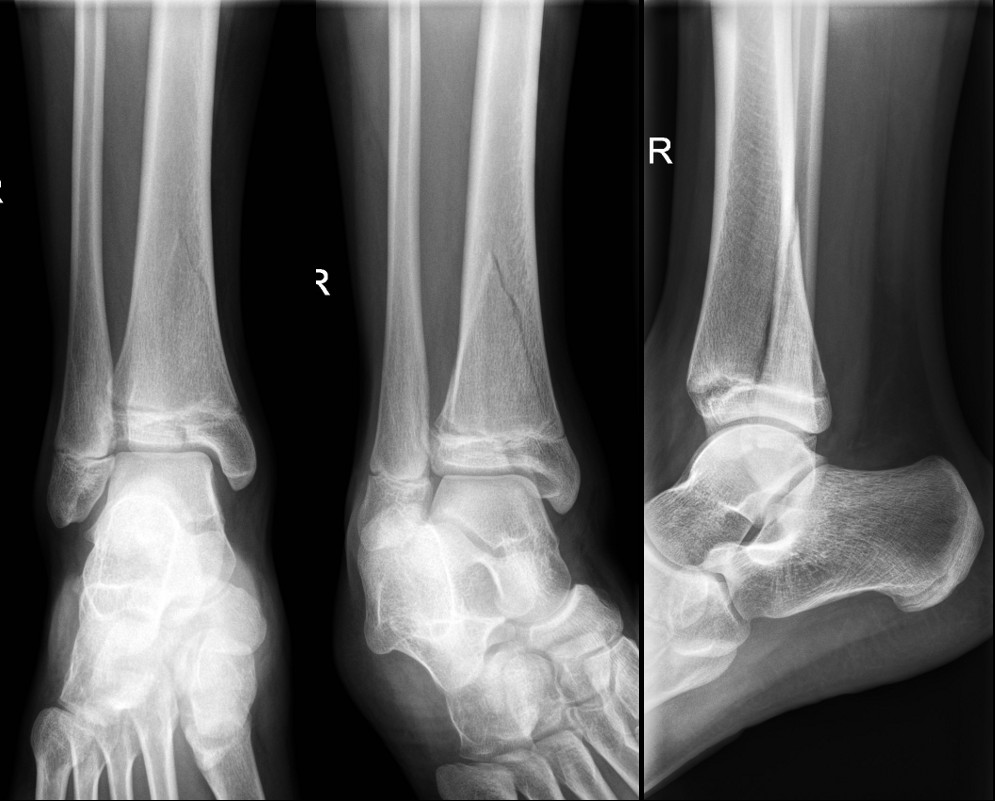

Salter-Harris III fracture of medial malleolus – requires internal fixation

Triplane fracture of distal tibia